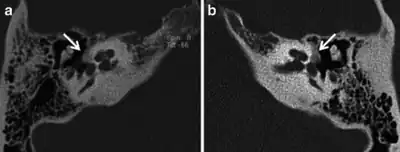

Images of the right a) and left (b) hypodense demineralised plaques arrow consistent with fenestral otosclerosis

Imaging is usually not pursued in those with uncomplicated conductive hearing loss and characteristic clinical findings. Those with only conductive hearing loss are often treated medically or with surgery without imaging. The diagnosis may be unclear clinically in cases of sensorineural or mixed hearing loss and may become apparent only on imaging. Therefore, imaging is often performed when the hearing loss is sensorineural or mixed.

A high-resolution CT shows very subtle bone findings. However, CT is usually not needed prior to surgery.

Otosclerosis on CT can be graded using the grading system suggested by Symons and Fanning.[16]

- Grade 1, solely fenestral;

- Grade 2, patchy localized cochlear disease (with or without fenestral involvement) to either the basal cochlear turn (grade 2A), or the middle/apical turns (grade 2B), or both the basal turn and the middle/apical turns (grade 2C); and

- Grade 3, diffuse confluent cochlear involvement (with or without fenestral involvement)